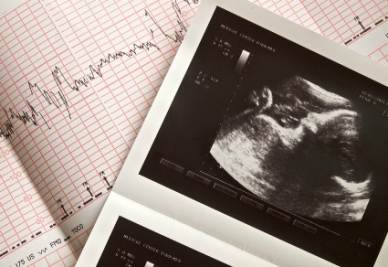

In Italia ogni anno circa 180.000 famiglie subiscono un lutto perinatale. Infatti ogni 6 gravidanze, una esita con la morte del bambino. Essere genitori, per molti, è un percorso irreversibile che inizia sin dal giorno in cui si è effettuato il test di gravidanza. Da quel giorno inizia un percorso fatto di sogni, desideri, speranze che si spezzano a

seguito dell’evento luttuoso che li colpisce. Perdere un figlio in grembo è una perdita che genera un dolore ed un lutto pari a qualsiasi altro tipo di perdita. Molto spesso questo dolore è amplificato dai sensi di colpa, dai dubbi, dalle domande circa le cause e le responsabilità che hanno portato a questo evento.